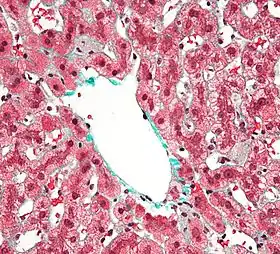

![]() مركز الفصيص خلية كوبفر، ولها هيولي حبيبي رمادي اللون، في كبد مصاب منقذ. خزعة الكبد. صبغة ثلاثية الألون. | |